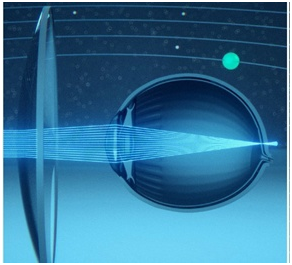

На первой схеме представлено здоровое глазное яблоко: свет фокусируется в макулярной зоне сетчатки, формируя четкое изображение.

Схема традиционной коррекции миопии:

Часть света в периферической зоне уходит за сетчатку, то есть возникает периферический гиперметропический дефокус.